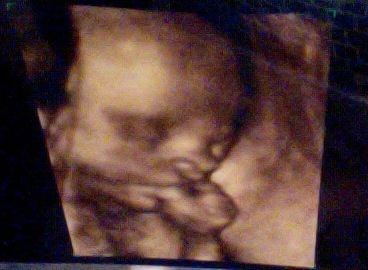

All is going well with the pregnancy at present, and our baby girl (that’s right, it’s a girl!) will be arriving this summer. Below is baby’s first solo photo shoot:

Pregnancy Care in China: Many of you are asking about the level of healthcare at our hospital. We’re pretty happy so far. Earlier this month we had a gestational diabetes screening test followed by a fetal cartographic scan. They are keeping an eye out for preclampsia and other disorders without being overly invasive. Lauren has had extensive blood work done, and her weight (and the baby’s) is tracked monthly. We also have a fetal heart monitor at home, basically a Doppler ultrasound where we can check the baby’s daily heart rate. We pre-paid at our hospital for the prenatal plus delivery packages, which totaled around $5,000. Not cheap by local standards, not cheap by Cube Abandoning standards but decent considering the amount of testing we’re getting each month. The baby’s first close up photo at the top of this blog is from a 4D ultrasound, advanced technology in any country and readily available here along with a technician who knew her stuff! So the care is good, but having never been hospitalized or spent serious time in a US hospital we don’t know how to compare it to prenatal care back home.